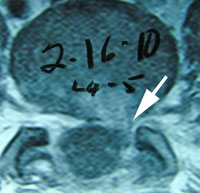

Probably no area of chiropractic spinal manipulation is as challenged as treating the post-surgical patient who is the same, worse, or disenchanted with their surgical outcome. Certainly, the opportunity to treat the patient before surgical intervention is best. When confronted with this post-surgical patient, however, the chiropractic physician proceeds as if with a patient who has not had surgery. i.e. The chiropractor will proceed with the careful history and clinical examination to determine what is causing the pain. That cause may be within the surgical site or adjacent to it. In treating the post-surgical spine, fusion or no fusion is a dictator of care. If there is a fusion, spinal manipulation is given to adjacent levels of the spine to the fused area. If there is no fusion, the doctor carefully proceeds as if no surgery. Some motion may be possible within the spine depending on the surgical procedure performed. (11)

Distraction Reverses Disc Degeneration

Discs have been seen to regenerate. Following 28 days of compression in rabbit discs which caused degeneration and then given 28 days of distraction applied, discs were seen to reverse their degenerative change with regenerative evidence. This was seen on mri study. Distraction results in disc rehydration, stimulated extracellular matrix gene expression, and increased numbers of cells. Disc distraction enhances hydration in the degenerated disc and may also improve disc nutrition via the endplates. (13)